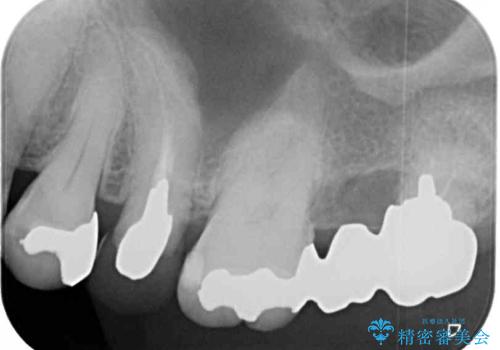

- 奥歯の銀歯とクラウンの縁から見えている歯根を気にして来院された患者様です。

歯根の見えている歯はセラミッククラウンに、詰め物の銀歯が入っている歯はセラミックインレーにて治療を行うこととしました。